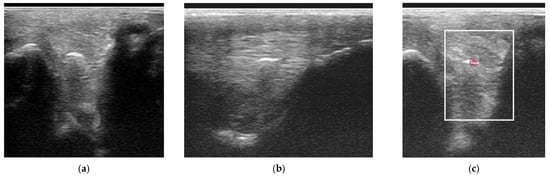

2.3.2. Power Doppler Examination

Power Doppler examination was included for horses examined from 2014 onwards to monitor vascular activity. This was initially performed in a standing position, to assess hypoechoic regions compatible with blood vessels, although if no signal was detected, the examination was repeated in a non-weightbearing position. Hypoechoic regions were assessed in several orientations and for at least two minutes and with the minimal pressure required to achieve adequate image quality, but to avoid false negative results by excessive compression. No sedation was used for examinations to avoid interference with the detection of neovascularisation. Only vascularisation inside a branch was considered a positive finding. If a positive signal was detected, a video clip of several seconds with variable angles was recorded. Power Doppler signal was classified as absent, mild, moderate or severe (Figure 1).

Figure 1. Transverse power Doppler ultrasonographic images of suspensory ligament branches representing the grades of power Doppler signal, from absent to severe, adapted from Szkudlarek et al. [24]. In all images, palmar is to the right.

Power Doppler examination was performed in 62/89 branches (67.4%). Doppler signal was present in 59/62 (95.2%) branches (Figure 5, Figure 6, Figure 7 and Figure 8) and absent in three branches. At the initial examination, Doppler signal was classified as mild in 22/62 branches (35.5%), moderate in 25/62 (40.3%) and severe in 12/62 (19.4%) branches. Doppler signals persisted in follow-up examinations, despite treatment, in 17/62 branches (27.4%) (Figure 7).

Figure 5. Twelve-year-old Warmblood mare; (a) B-mode transverse ultrasonographic image of the left forelimb lateral suspensory branch five days after injury. There is a well-defined hypoechoic region (red arrow) within the branch, and a hypoechoic region subcutaneously consistent with periligamentous oedema (blue arrow); (b) power Doppler image at the same level as (a). There is severe power Doppler signal. (c) Transverse power Doppler image one month after injury; there is no periligamentous oedema, the lesion in the branch is less well-defined and there is no power Doppler signal within the branch.

Figure 6. Twelve-year-old Warmblood mare with right hindlimb lameness and abduction of the limb during protraction. (a) Transverse, (b) longitudinal (distal to the right) and (c) transverse power Doppler images of the lateral branch of the suspensory ligament. There is a linear hyperechoic region causing acoustic shadowing. There is mild power Doppler signal localised around the hyperechoic region.

Figure 7. Transverse (left) and longitudinal (right) ultrasonographic images of the lateral branch of the suspensory ligament (SL) of a hindlimb of a 15-year-old purebred Spanish horse (PRE), acquired 2 weeks after injury, with a non-healing suspensory branch desmitis. The SL branch is enlarged with large hypoechoic regions and loss of long linear parallel echoes in the longitudinal image. There is also substantial subcutaneous echogenic tissue consistent with periligamentous fibrosis. Power Doppler signal was graded severe and persisted despite treatment. The horse was retired.

Figure 8. Longitudinal ultrasonographic images of the lateral branch of the suspensory ligament (SL) of a right forelimb of a four-year-old gelding (a,b) before treatment and (c) six months later; proximal is to the left. (a) There is loss of long linear parallel echoes in the dorsal aspect of the SL close to the enthesis. There is irregularity of the surface of the proximal sesamoid bone (PSB). (b) There was mild Doppler signal at the enthesis on the apex of the PSB. (c) At six months after treatment, a hypoechoic lesion persists, but there is no longer any power Doppler signal.